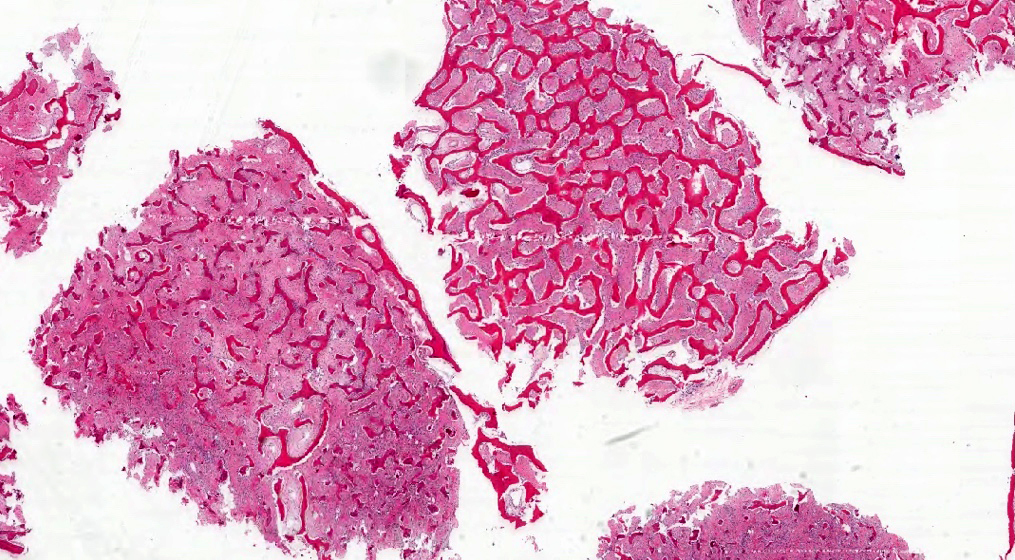

Microscopic (histologic) description

- Branching and anastomosing irregular trabeculae of woven bone ("C" and "S" shapes) with no conspicuous osteoblastic rimming

- No / rare osteoclasts

- Intervening fibrous stroma containing cytologically bland spindle cells, without prominent cytologic atypia

- Mitotic figures rare

- Stromal changes, including myxoid change and fatty metaplasia, may be seen in some cases (BMC Musculoskelet Disord 2003;4:20)

- Secondary aneurysmal bone cyst-like changes may also be seen (Turk Patoloji Derg 2018;34:234)

- Fibrocartilaginous dysplasia: uncommon variant containing variable proportions of cartilaginous differentiation and enchondral ossification (Am J Surg Pathol 1993;17:924)

- Growing collagen (Sharpey's fibers) may form perpendicular to the sites of bone formation but are not essential for diagnosis (Oral Dis 2017;23:697)

Microscopic (histologic) images